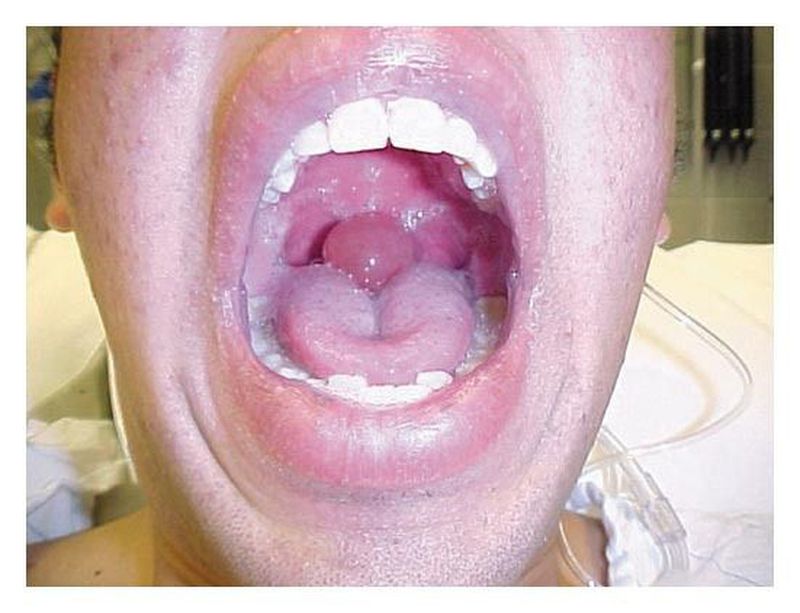

A 19-year-old man without a history of asthma or allergies presented to the emergency department with difficulty in breathing. He had snorted and smoked cocaine three hours before presentation, after which tightness of the throat developed, along with throat pain and difficulty in swallowing. On examination, the patient was drooling and spoke with a muffled voice. On admission, his vital signs revealed mild tachycardia and tachypnea, without hypoxemia on pulse oximetry. His uvula was markedly edematous (2 cm in diameter) without erythema. There was no stridor or wheeze. The symptoms improved over a period of five hours after treatment with epinephrine, antihistamines, and corticosteroids. Uvular angioedema, or Quincke's disease, was diagnosed and was believed to have resulted either from allergy to cocaine or from direct thermal injury. Andrew Kestler, M.D. Linda Keyes, M.D. University of Colorado Health Sciences Center, Denver, CO 80262 source: nejm.org